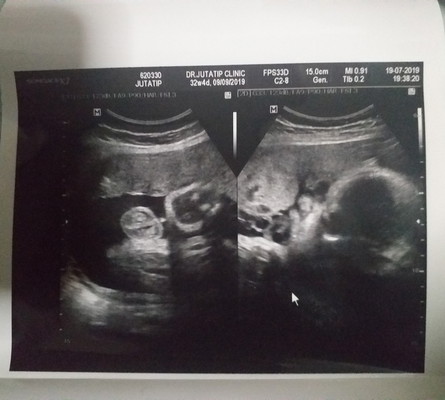

32+4 w น้ำหนักน้อง 2015 กรัม แต่มีคนบอกว่าน้ำหนักน้องน้อยไป ขอความคิดเห็นหน่อยค่ะ ?

คุณหมอบอกว่าน้องนน.น้อยไปใหมคะ เราว่าไม่น้อยนะ หลังจากนี้นน.น้องจะเพิ่มเร็วขึ้นกว่านี้ ส่วนคนที่ชอบทักว่าท้องเล็กน้องตัวเล็กสารพัดจะพูดหมอบอกว่าอย่าไปสนใจซึ่งจริงค่ะ ดีแต่พูดนี่นนี่บางคนเก่งกว่าหมอ